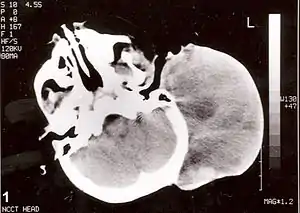

Існує чотири підтипи рабдоміосаркоми — ембріональна рабдоміосаркома (англ. embryonal rhabdomyosarcomas), альвеолярна рабдоміосаркома, плеоморфна рабдоміосаркома (англ. pleomorphic rhabdomyosarcoma) та клітина веретена / склерозуюча рабдоміосаркома[4]. Ембріональні та альвеолярні є основними групами, і ці типи є найпоширенішими саркомами м'яких тканин дитячого та юнацького віку. Плеоморфний тип зазвичай зустрічається у дорослих. Зазвичай ця пухлина вражає м'язи кінцівок[5].

RMS може виникати в будь-якому місці м'яких тканин в організмі, але, головним чином, виявляється в голові, шиї, очниці, сечостатевих шляхах, статевих органах та кінцівках. Чітких факторів ризику немає, але хвороба пов'язана з деякими вродженими аномаліями[7][10].